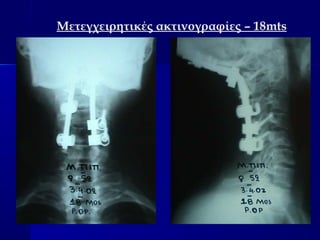

Μετεγχειρητικές ακτινογραφίες – 18mts